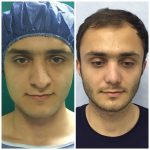

دکتر عیسی عبدی در رشت

دکتر عیسی عبدی در رشت

– متخصص جراحی فک , پلاستیک صورت و بینی

جراحی فک , پلاستیک , صورت وبینی

جراحی ترمیمی و زیبایی فک و صورت و جمجمه و گردن